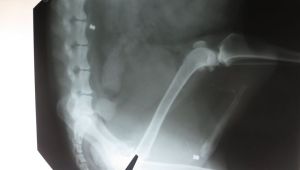

Передріздвяне: у Львові знайшли собаку з поламаними лапами і кулями в тулубі. Священник уже не вірить у загальну набожність ЛьвоваУ Львові на проспекті Чорновола знайшли собаку з поламаними лапами і кулями в тулубі. Священник Роман Грицишин рятує тваринку у ветеринарній клініці і не вірить у загальну набожність Львова.